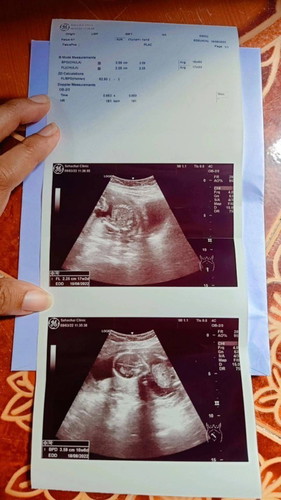

วันนี้ไปอัลตร้าซาวด์ดูเพศมา 17w2d คุณหมอบอกว่าตัวน้องยังเล็กมาก ยังดูเพศไม่ได้เลย

วันนี้ไปอัลตร้าซาวด์ดูเพศมา 17w2d คุณหมอบอกว่าตัวน้องยังเล็กมาก ยังดูเพศไม่ได้เลย คุณหมอบอกอีกว่าประมาณ 20wจะเห็นชัดเจน มีแม่ๆคนไหนเป็นเหมือนเค้ากันบ้างค่ะ👶

17w3d ค่ะ ไปอัลตราซาวด์วันนี้เหมือนกันค่ะ หมอบอกเหมือนจะเป็นผู้ชาย แต่น้องยังเล็กมากเห็นไม่ค่อยชัด เดี๋ยว 20w หมอจะนัดตรวจอีกทีค่ะ สู้ๆนะคะ ลุ้นไปด้วยกันค่าาา 🥰🥰

ของเค้าหมอบอกว่าเหมือนน้องยกขานั่ง เหมือนจะผช. แต่น้องตัวเล็กมาก เลยเห็นไม่ชัดมาก คุณหมอนัดอีกที 20สัปดาห์

นี่หมอบอกว่าเหมือนยกขาขึ้น แต่ยังเห็นไม่ชัดเลย ตัวเล็กมาก